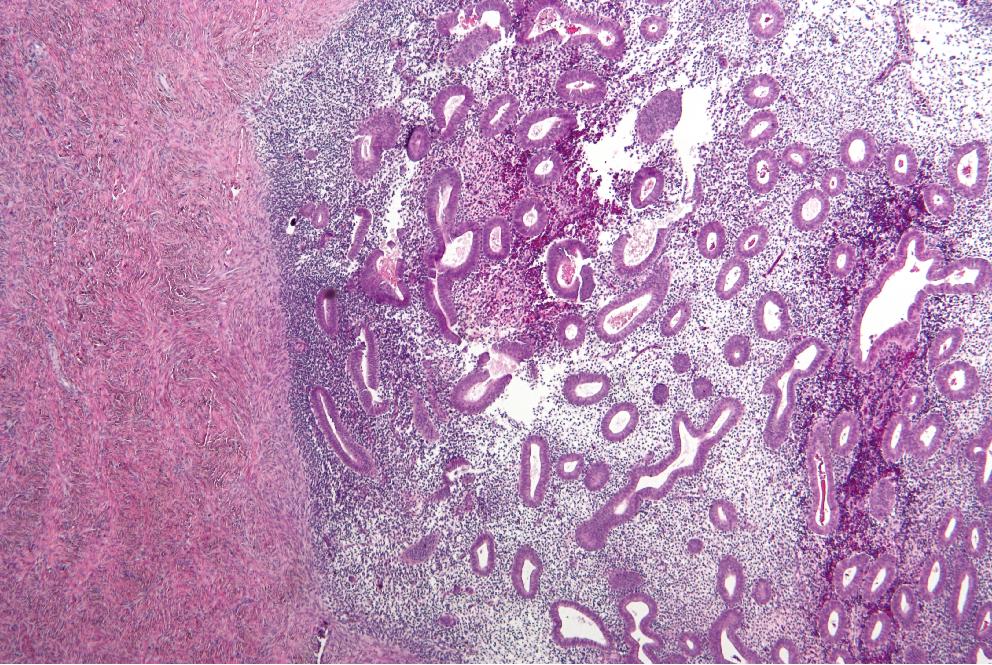

Endometriosis

El dolor de ovarios o localizado en la parte baja del abdomen es uno de los principales síntomas de la endometriosis, una condición que se produce cuando las células del endometrio crecen fuera del útero y provocan la formación de bultos sangrantes. También suelen aparecer otros signos y síntomas como dolor en las relaciones sexuales, alteraciones menstruales, problemas para quedar embarazada, etc.

No es una afección fácil de diagnosticar, por lo que ante el manifiesto de estos síntomas es importante que acudas a tu médico y te realices las pruebas oportunas. El facultativo decidirá cuál es el tratamiento adecuado en función de las particularidades de cada caso en concreto.